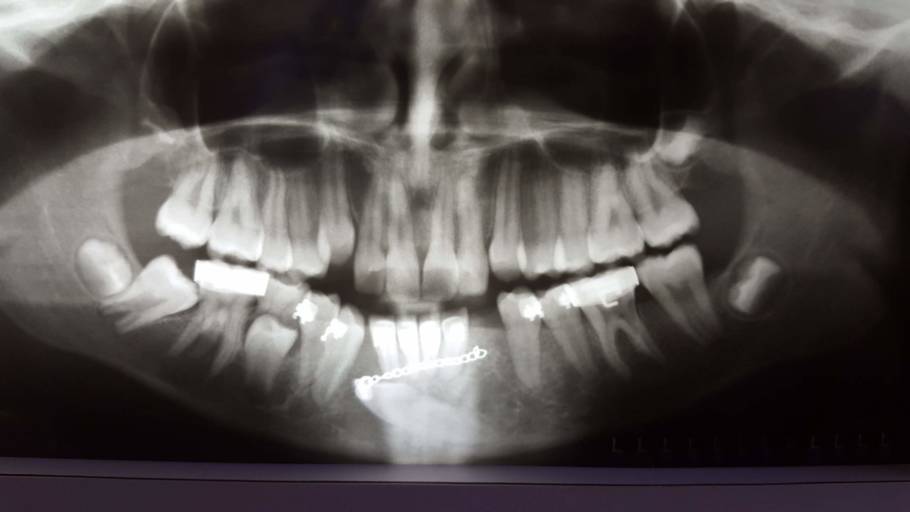

Hi. My name is Olivia and I recently have been experiencing an overwhelming amount of anxiety as a result of a shifting of my teeth because of the change that the way my jaw sits when I close my mouth and the inability to smile the same with my teeth closer as before. I know that this isn’t not a proper question to ask a dentist, but I am really looking for some at home ways to shift teeth. I fully accept any risks that I could do to my teeth, but this will greatly improve the quality of my life if I can succeed in this. I have included a picture of the teeth in question. I am looking to switch the positioning of the front bottom crowded two teeth so the one that’s is currently in the back is in the front, not to make them straight. Thank you so much for your time, and this means so much to me.